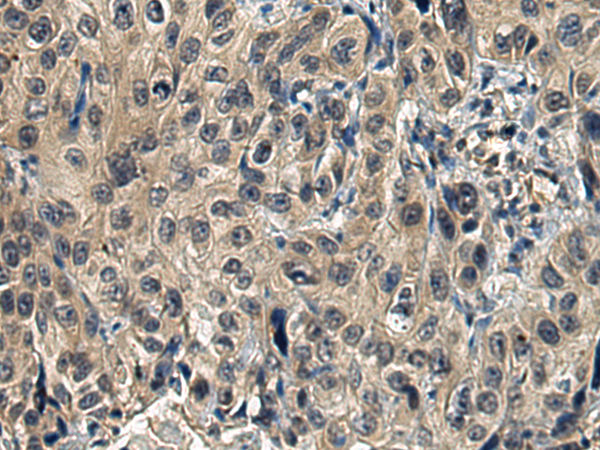

分类: 科研抗体货号: P11267别名: MG1; MUC5; MUC9; MUC-5B应用: WB,IHC反应种属: Human